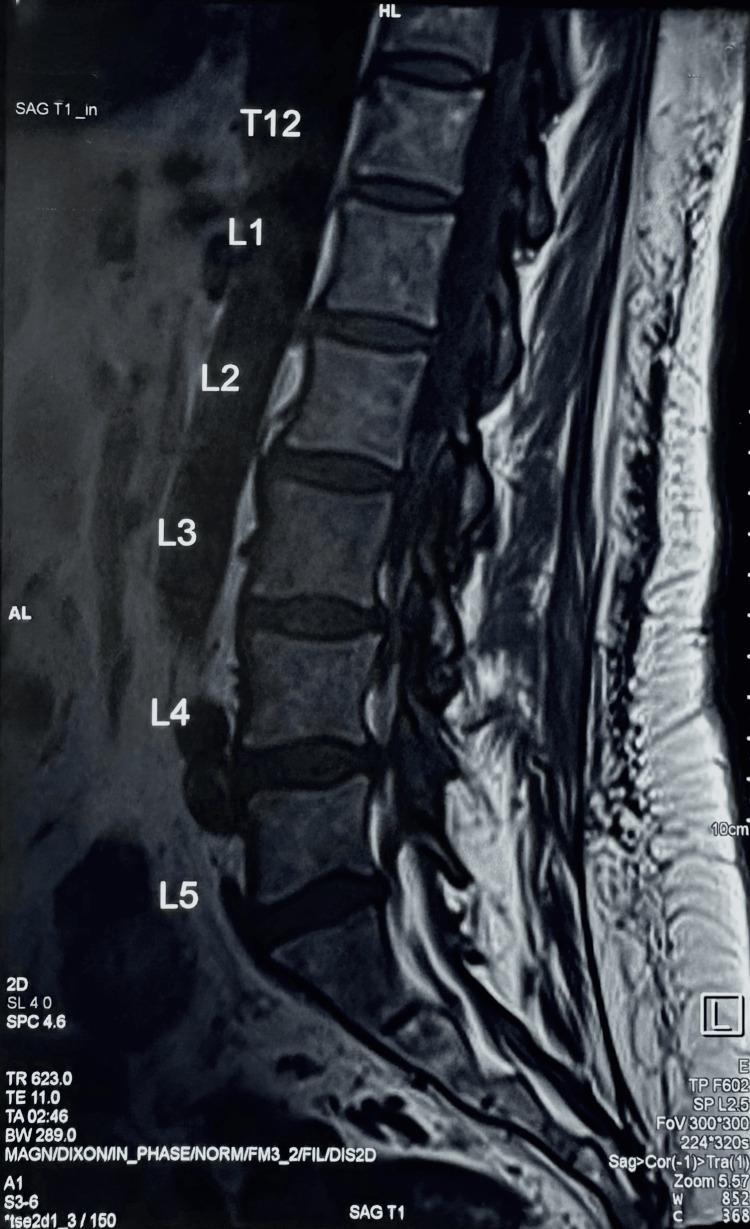

A 67-year-old woman presented to a chiropractor with a four-week history of neck and low back pain, lower extremity paresthesia, profound fatigue, and cutaneous pallor. Previous cervical radiographs had revealed multilevel degenerative spondylosis. However, abnormal hematological indices, including severe thrombocytopenia and anemia, prompted concerns of an underlying hematopoietic malignancy. Interdisciplinary collaboration facilitated expedient hematological assessment, confirming acute lymphoblastic leukemia (ALL), as evidenced by lymphoblasts in a peripheral blood smear and bone marrow biopsy. Karyotyping detected a Philadelphia chromosomal mutation; the patient therefore received oral targeted tyrosine kinase inhibition coupled with serial intrathecal chemotherapy. Complete remission was achieved. However, sensorimotor symptoms persisted due to herpetic neuralgia secondary to immunosuppression. This complex case underscores the role of chiropractors as primary contact clinicians in identifying sinister pathologies underlying musculoskeletal complaints via judicious history-taking, physical evaluation, and interpretation of investigational findings. Interprofessional collaboration is pivotal in formulating an effective therapeutic strategy to improve the prognosis of patients with this disease.

一名67岁女性因颈部和下背部疼痛、下肢感觉异常、极度疲劳和皮肤苍白等症状持续四周,前来就诊于一名脊椎按摩师。先前的颈椎X光片显示有多节段退行性脊柱病。然而,包括严重血小板减少症和贫血在内的异常血液学指标引发了对潜在造血系统恶性肿瘤的担忧。跨学科合作促成了快速的血液学评估,确诊为急性淋巴细胞白血病(ALL),外周血涂片和骨髓活检中的原始淋巴细胞证实了这一诊断。核型分析检测到费城染色体突变;因此,该患者接受了口服靶向酪氨酸激酶抑制治疗并辅以鞘内化疗。实现了完全缓解。然而,由于免疫抑制继发的疱疹性神经痛,感觉运动症状持续存在。这个复杂的病例强调了脊椎按摩师作为初级接诊临床医生的作用,即通过审慎的病史采集、体格检查和对检查结果的解读,识别肌肉骨骼症状背后的隐匿病变。跨专业合作对于制定有效的治疗策略以改善该疾病患者的预后至关重要。